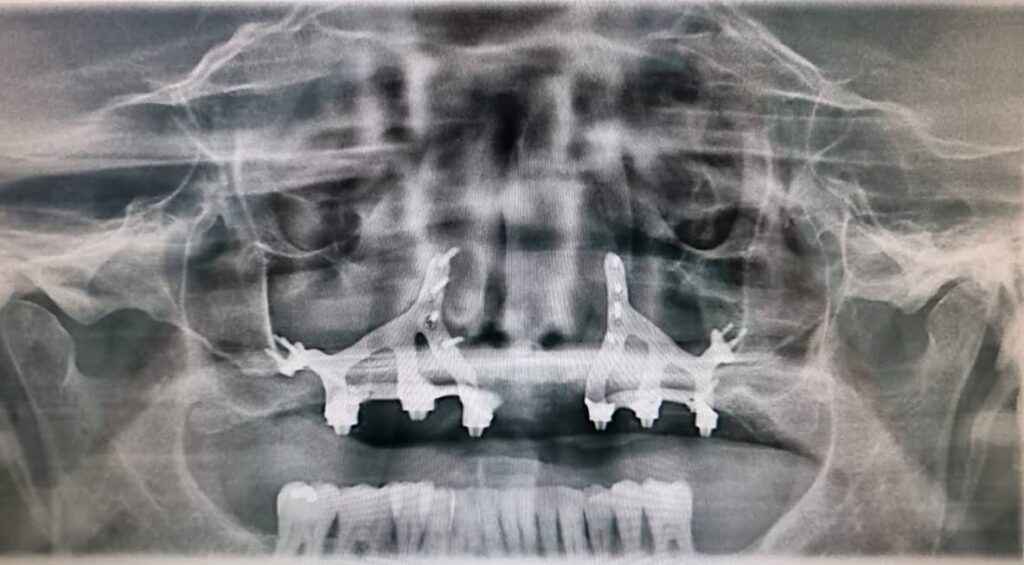

En Clínica Dental Edo, especialistas en implantes dentales en Barcelona, realizamos siempre un estudio completo con ortopantomografía, CBCT/TAC 3D y analítica antes de recomendar un diseño u otro. El material y el tipo de implante son importantes, pero lo fundamental es elegir la opción más segura y predecible para cada paciente.

Implantes yuxta-óseos o subperiósticos

Se apoyan sobre el hueso, pero no se insertan dentro de él. Antiguamente se indicaban en pacientes con gran pérdida ósea, donde no era posible colocar implantes endo-óseos. Con los avances en regeneración ósea y técnicas modernas, su uso hoy es muy excepcional.

Estos implantes se diseñan a medida, pero su mayor inconveniente es que tienen menos estabilidad a largo plazo y requieren un mantenimiento exhaustivo.

Implante dental cigomático

En pacientes con pérdida ósea severa en el maxilar superior, se pueden utilizar implantes más largos que se fijan en el hueso cigomático (pómulo). Son una solución avanzada para casos donde los implantes convencionales no son viables sin injertos.